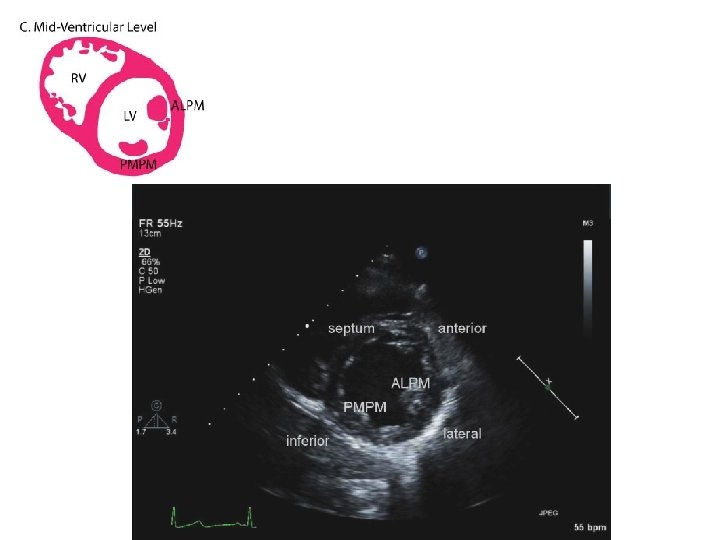

SUBCOSTAL SHORT AXIS